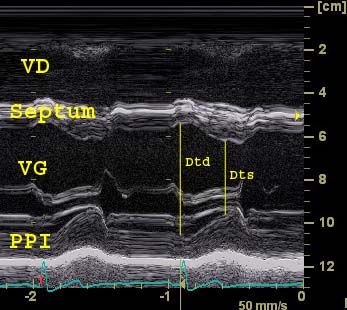

...en mode TM: la ligne de tir TM, perpendiculaire au grand axe du septum, est successivement positionnée pour analyser 3 zones d'intérêt: Cavité ventriculaire gauche, valve mitrale, aorte/oreillette gauche. Les mesures TM sont fiables et reproductibles (Ep=épaisseur; td=télédiastole; ts=télésystole)

Mesures utiles

Ep septum td ≤ 11mm

Ep paroi post VG td ≤ 11mm

Diamètre VG td (Dtd) ≤ 56 mm

Diamètre VG ts (Dts)

Fraction raccourcissement: (Dtd-Dts)/Dtd 36±6%

Ratio (td) VD/VG < 50%

Etude de la fonction contractile (FR)